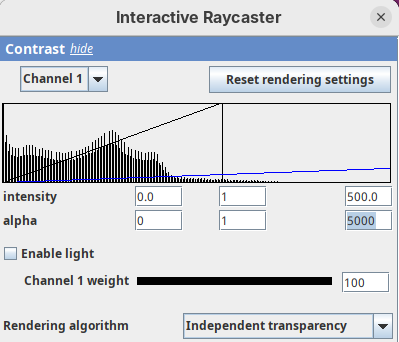

Contrast

The Contrast section shows a histogram of pixel intensities of the image for each channel, which we can choose using the dropdown menu. We can set the minimum, gamma, and maximum values for the intensity and alpha (transparency) properties of each pixel. The weight option controls the general opacity of the channel (0=invisible, 100=visible). There’s also more advanced options like lighting and rendering algorithm which we’ll simply use the default states as they are usually good for most use cases.

Adjusting the intensity and alpha values is the most impactful way to improve the 3D rendering. With the intensity setting we can define which pixel value in the image corresponds to total black (minimum) and which corresponds to total white. It’s the same as in the standard Brightness & Contrast tool. By default, 3Dscript will load these values from the original stack. In this case, it loaded min=3 and max=521.

Let’s change these values to see how it impacts the 3D rendering.

- Change the intensity minimum to

250.

You will see that the darkest parts of the rendering will become even darker and no longer visible. We are losing real information from the data; we do not want that.

- Set the

minto0, for now. - Then, change the

maxto250.

The brightest parts of the rendering will become all white. It is so bright that we can no longer resolve details of the surface. We are losing information and also do not want that.

- Set the

maxto500.

Note that when you change an intensity value, the min/max black line in the histogram moves. You can also grab the line and move it manually to change the values.

The blue line represents the alpha values. In 3D rendering, a pixel has a transparency value linked to its intensity. The alpha min defines the value for full transparency and the max the value for full opacity.

- Set the alpha

minto250.

This will make darker pixels more transparent and information gets lost.

- Set it to

0.

By default 3Dscript sets the gamma value of alpha to 2.0. That’s a good default for fluorescence microscopy (see the next dataset below), but since this is MRI data, we need to tweak it a little differently.

- Set the alpha gamma value to

1.0.

Note that this improves the visualization as the head’s surface becomes better visible.

- Now set the alpha

maxto250.

The surface will become even more solid because we are defining that pixels that have a value above 250 will be fully opaque.

- To compare, set alpha

maxto5000.

You will notice that the sample will become more transparent. Even the brain inside the skull will be visible.

- Set alpha

maxback to500.

Generally, setting the intensity and alpha to the same values is a good starting point for optimizing the rendering.